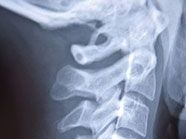

Ein Krankenhaus in Australien hat einen Patienten trotz eines gebrochenen Genicks wieder nach Hause geschickt.

Curtis war mit starken Schmerzen an einem späten Freitagabend in die Notaufnahme gefahren, nachdem er und ein Freund versehentlich mit dem Kopf zusammengestoßen waren. In der Notaufnahme sei ihm mitgeteilt worden, dass die Röntgenabteilung bereits geschlossen sei und er nach Hause gehen und Schmerztabletten nehmen solle.

Als er am darauffolgenden Montag nach einem qualvollen Wochenende schließlich geröntgt wurde, stellten die Ärzte fest, dass er sich einen Halswirbel gebrochen hatte, was sein Rückenmark zu durchtrennen drohte. “Der Arzt sagte mir: ‘Nicht bewegen, Sie haben ein gebrochenes Genick'”, sagte der Mann. “Als er sagte, dass ich Glück habe, noch am Leben und nicht querschnittsgelähmt zu sein, war ich erschüttert.” Das Krankenhaus entschuldigte sich öffentlich bei dem Patienten. In Zukunft würden Patienten mit ähnlichen Symptomen sofort geröntgt